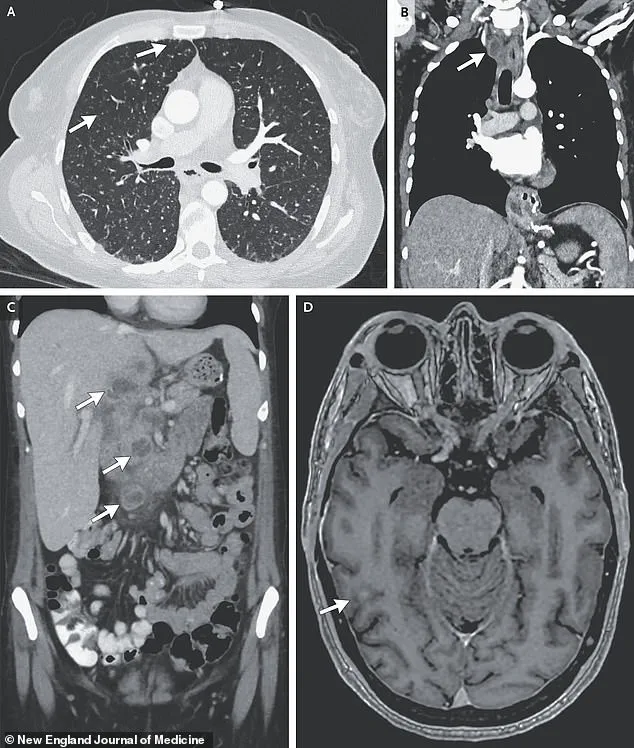

Further imaging revealed lesions in multiple organs, including the liver, lymph nodes, pancreas, and brain—indications of a systemic infection.

After nine weeks of testing, including biopsies and bacterial cultures, doctors confirmed the presence of *Mycobacterium tuberculosis*, the pathogen responsible for tuberculosis (TB).

This diagnosis marked a rare but severe case of disseminated TB, a form of the disease that spreads beyond the lungs to affect multiple organs.

The severity of her condition was underscored by the fact that the TB had reached her brain, a rare but particularly dangerous complication.

If left untreated, the infection can progress to severe respiratory failure, extensive lung damage, and even the spread of bacteria to other organs, such as the brain, liver, and pancreas.